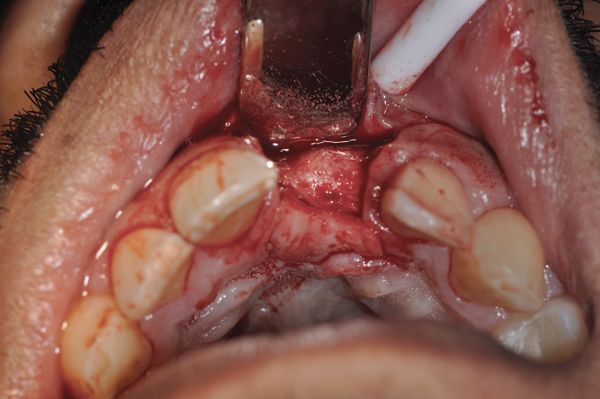

Fig 12. (Case 2) Tooth No. 9 was extracted; the buccal plate was dehisced.

Figure 12

Fig 13. Flap elevated 6 months after d-PTFE barrier and bone graft were placed; the barrier was removed after 4 weeks. This photograph shows the buccal plate regenerated.

Figure 13

Fig 14. An implant was inserted in regenerated bone.

Figure 14

The four presented cases shown in Figure 1 through Figure 25 were all treated in a similar manner as outlined in detail in the captions for the first case (Figure 1 through Figure 11). In all four cases, teeth with pathosis were removed, buccal and lingual flaps were elevated, and sites were surgically debrided. A Cytoplast d-PTFE barrier was sized and inserted usually under the buccal flap, the bone graft was added, the barrier was then tucked under the lingual flap, and the flaps were sutured. Bone grafts were used in all of the cases, because buccal bony plates were resorbed and the bone graft helped support the barrier.